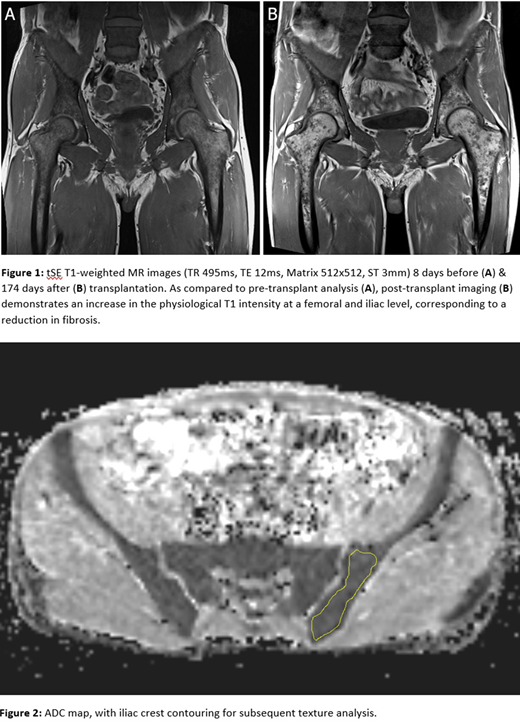

The selected MRI parameters showed substantial modifications between the first and second exams. T1 and STIR sequences demonstrated a decrease in bone marrow fibrosis (Figure 1). ADC values increased at pre-specified target points (iliac crest, pre-transplant: 0.762, post-transplant: 0.901; femur, pre-transplant: 0.77, post-transplant: 0.808). Moreover, among 300 features analyzed (Figure 2), 20 presented changes potentially related with bone marrow restoration. Concomitant STRs analysis showed a full donor chimerism status.

We report the case of a 45-year-old man diagnosed with triple-negative MF who was eligible for HCT following progression after a previous procedure. A pre-transplant trephine biopsy showed grade III fibrosis, according to the WHO 2016 classification. CD34+ cells were found to comprise 10%-15% of cells. He underwent MRI 8 days before bone marrow transplantation from a haploidentical donor. A second, comparative MRI was performed 6 months after HCT; concurrent chimerism was estimated through Short Tandem Repeats (STRs) analysis. A multiparametric protocol was applied, including intravoxel incoherent motion (IVIM) diffusion-weighted imaging, Dixon GRE with fat fraction calculation, and Turbo Spin Echo T1 and STIR sequences. MRI examination was performed on a 3 Tesla MRI machine and included lumbar segments L4 and L5, pelvis, sacral bone, and coccyx. A phased-array surface coil was applied to optimize signal-to-noise ratio. Finally, radiomics and texture analysis were performed on ADC sequences using specific image software post-analysis (Slicer 3D v.4.10.2).